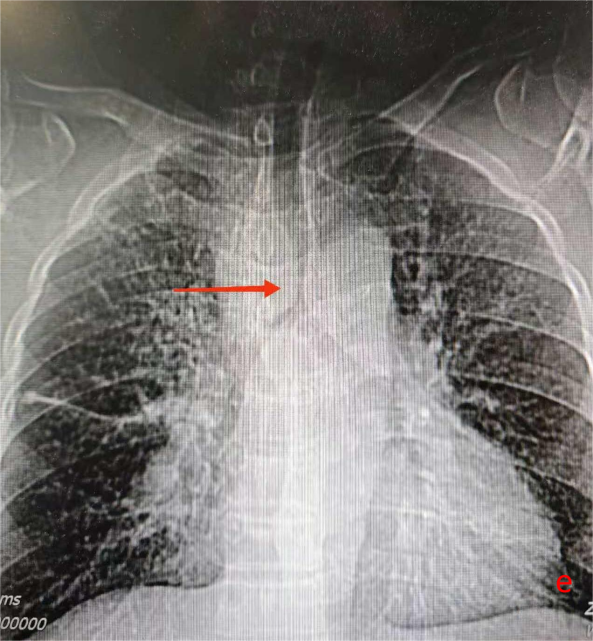

意外却在2025年9月悄然发生。当时W先生正在外院准备接受放疗,期间呼吸困难症状急剧加重,不仅无法耐受下床活动,还伴随咳嗽咳白黏痰。紧急复查CT显示,他的气管下段已出现重度狭窄,这一状况不仅严重威胁生命安全,也让原本的放疗计划因风险过高而难以实施。危急时刻,W先生前往温岭市第一人民医院寻求进一步救治。

2025年10月10日,手术在全麻下顺利开展。医护团队通过支气管镜的精准引导,将支架成功植入患者气管狭窄部位,整个过程平稳有序。术后奇迹很快显现:W先生的呼吸困难症状当场明显缓解,复查胸片提示气道下段通畅度显著改善,没过多久便能正常进行日常活动。短暂恢复后,他顺利返回继续接受胸部肿瘤放疗,整个放疗过程进展顺利,胸部肿瘤明显缩小。

同年12月19日,W先生再次来到温岭市第一人民医院,在接受肿瘤相关治疗的同时,医护团队为他实施了支架取出手术。术后检查显示,他的气管保持通畅,呼吸顺畅,目前生活状态良好,已恢复正常生活节奏。